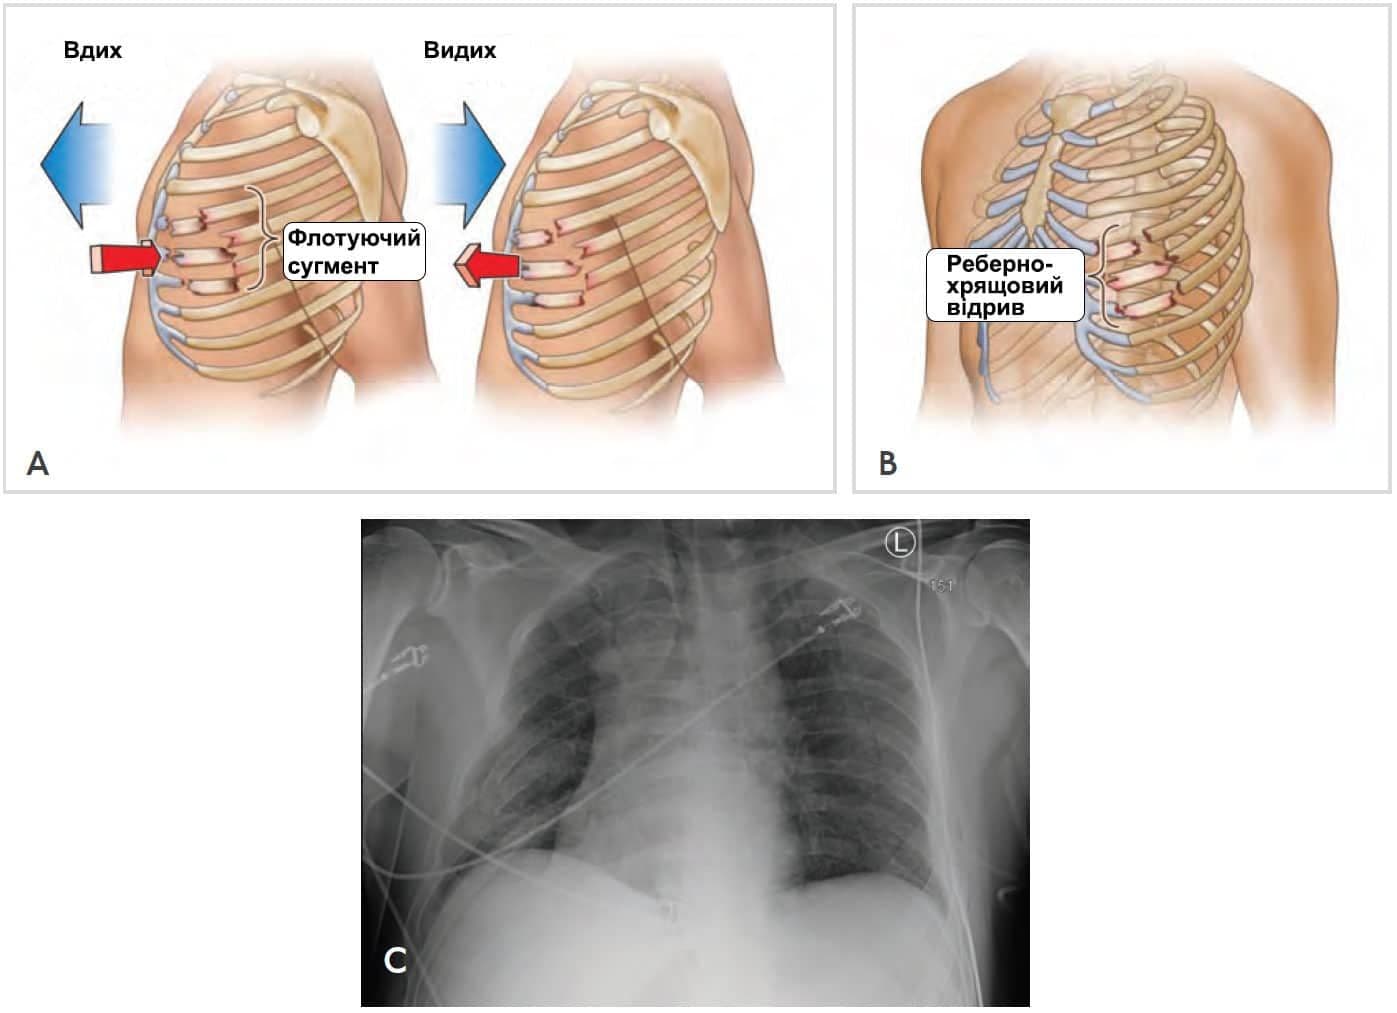

Флотуюча грудна клітка визначається як сегмент грудної клітки, котрий втратив кісткову підтримку від решти кісткового каркасу грудної клітки. Цей стан зазвичай виникає, коли є перелом кількох ребер (два і більше ребра зламані у кількох місцях) або внаслідок відділення реберного хряща від груднини (Зобр. 4-9)

Зобр. 4-9. Рухлива грудна клітка. Наявність рухливого сегмента ребер призводить до порушення нормального руху грудної стінки. A. Рухлива грудна клітка від множинних переломів ребер. B. Рухлива грудна клітка внаслідок відділення реберного хряща від груднини. C. Звичайна рентгенограма, що показує травму грудної клітки, пов’язану з множинними переломами ребер. Сегмент грудної стінки не має кісткової цілісності з іншою частиною грудної клітки.

Забій легень – це пошкодження легень, зумовлене травмою грудної клітки. Кров та інші рідини накопичуються у легеневій тканині, що перешкоджує нормальній вентиляції та призводить до гіпоксії. Забій легень може також виникнути без переломів ребер чи забитої грудної клітки, зазвичай так відбувається у молодших пацієнтів з не повною осифікацією ребер. У дітей грудна клітка є більш гнучкою, тому вони отримують забої та внутрішні травми грудної клітки без переломів ребер.

У дорослих забій легень найчастіше трапляється разом з переломами ребер і є потенційним небезпечним для життя ускладненням. Розвиток респіраторного розладу скоріше є не значним. Обмежений респіраторний резерв у пацієнтів похилого віку може призвести до швидкого розвитку дихальної недостатності.

Флотуючий сегмент грудної клітки може бути виявлений під час огляду не одразу, особливо, якщо травма – дуже свіжа. Слабкість дихання, разом з забоєм та ателектазом можуть обмежувати рухомість грудної клітки. М’язи грудної клітки також заважають повній візуалізації нетипових рухів грудної клітки. Якщо травма викликає забій легень, то є ризик виникнення тяжкої гіпоксії. Обмеження рухів грудної клітки асоціюється з болем і супутнім забоєм легень та призводить до дихальної недостатності.

Спостереження нетипових рухів грудної клітки і крепітація ребер чи хрящових структур можуть спростити постановку діагнозу. Скоріш за все, рентген грудної клітки вкаже на наявність перелому ребер, але може не показати кістковохондральну сепарацію.